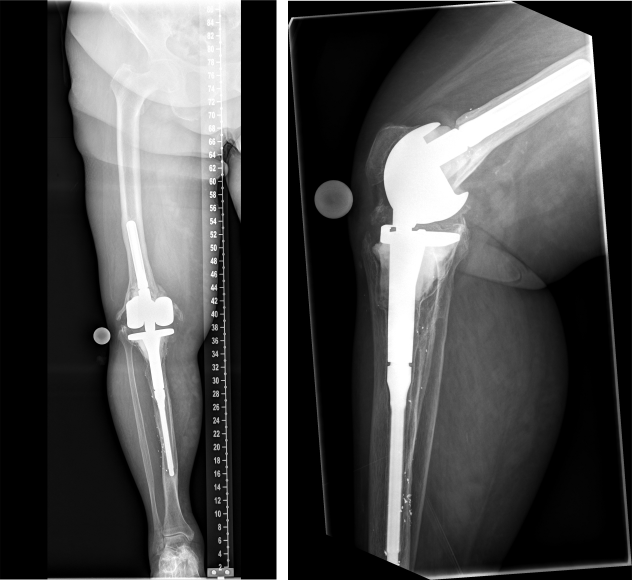

This is a report on a female patient aged 80 years at time of last surgery. The patient was first admitted to our center in 2016. Primary right-sided total knee replacement was carried out in 1994, revision surgery due to aseptic loosening was then performed in 2005. In 2016, aseptic loosening of the components was diagnosed again (Figure 1 [Fig. 1]). Revision surgery was carried out with distal femoral replacement (Figure 2 [Fig. 2]). In 2020, the patient presented to us with insufficiency of the extensor apparatus. According to the clinical picture, especially the macroscopic findings during surgery, infection could not be ruled out. Therefore, explantation of the components was carried out with implantation of a cement spacer. The histological and microbiological findings ruled out infection. Therefore, an intramedullary arthrodesis of the knee was carried out during the same hospital stay (Figure 3 [Fig. 3]). In 2022, the patient again complained of pain and we detected loosening of the femoral component. Despite the fact that no microbes were ever isolated in the right knee, we suspected low grade infection, as loosening occurred within less than 2 years accompanied by local signs of infection (Figure 4 [Fig. 4]). Explantation was carried out with implantation of a cement spacer with intramedullary carbon nails (Figure 5 [Fig. 5]). Yet, the histological and microbiological investigations ruled out infection.

Figure 1: Preoperative X-ray of the right knee joint (in 2016) showing aseptic loosening of the components

Figure 2: Postoperative X-ray of the right knee joint (in 2016) showing total knee and distal femoral replacement